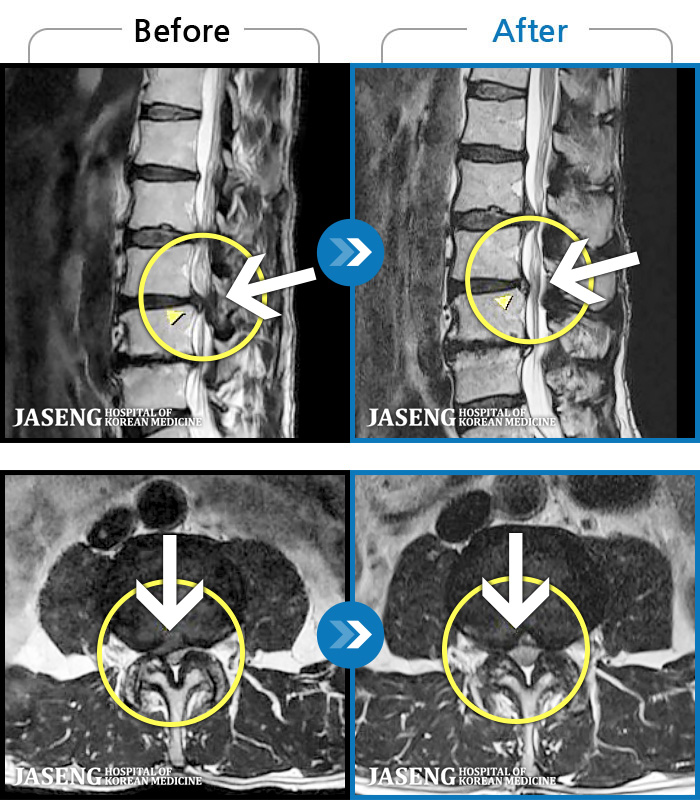

1,237 MRI ũ ʸ Ȯϼ.

㸮 ϻ .